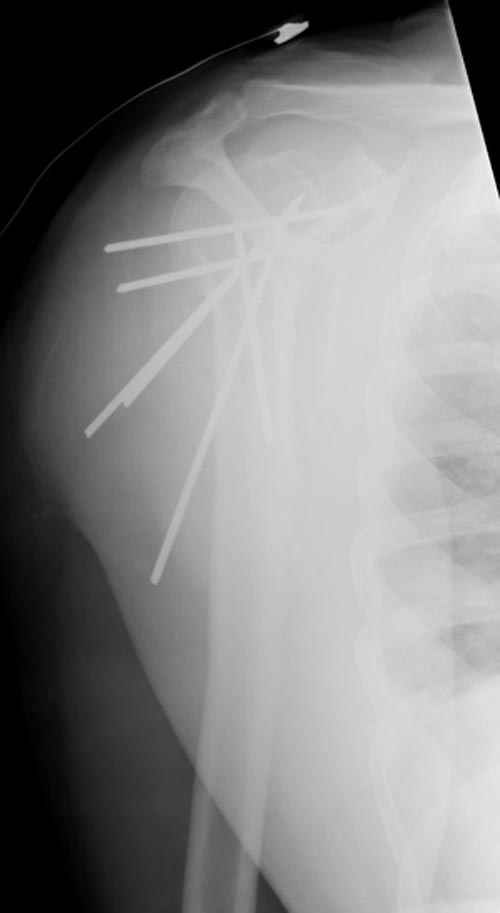

Женя, а как ты водишь спицы, в смысле, как делаешь входное отверстие, и как в него проводишь V-спицу? А то о дна из спиц, та, у которой не дошла до головки одна палочка буквы V, как-то выглядит на рентгенограмме, как будто или через очень большое отверстие введена, или каждая половинка через отдельные отверстия.

Мне кажется, проблема в том, что не все концы спиц зашли в головку, и зашедшие - недостаточно далеко прошли.

Спицы провожу по передней и задней поверхностям плечевой кости через 4,5 мм отверстия на разных уровнях.

Уточни - обе части буквы V вводишь в одно отверстие? А то по снимкам выглядит, что в разные.

V-спица проводится через 4,5 мм отверстие. Видимо, из-за разной длины вторая половина спицы *пролетела* мимо отверстия, что и привело к вторичному смещению костных фрагментов.

Здравствуй Женя. Во первых спицы, вводимые в головку плеча ретроградно, никогда не имели V-образную форму, если говорить о методике моей операции ЦИТО. Чтобы легче было запомнить Y-образную форму, вспомни крепление новогодних елочных шаров - очень демонстративно. Кроме того если ты внимательно посмотришь, то увидишь, что вся конструкция имеет некоторую кривизну по плокскости, величину, которой ты можешь задать сам. Сначала мы проводим проксимальный пучок, а в момент пересечения линии перелома мы

ротируем спицу таким образом, чтобы дистальный изгиб прямо противодействовал смещающим силам - поврот за ушко под контролем ЭОПа. Дистальный пучок стараемся провести так, чтобы его бранши расклинились и прошли по обе стороны предыдущего пучка, что создает дополнительное напряжение на

протяжении контакта. Для оценки правильности проведения спиц очень важно, чтобы ЭОП стоял строго перпендикулярно плоскости сустава, в противном случае - в рентгене есть эффект отбрасывания тени - прохождение косого луча дает удлиненное изображение спиыц и создается впечатление, что спица стоит уже в субхондральном слое. На первых операциях у нас было довольно частое несовпадение длины контрольной спицы и мы провизорно добавляли от 0,5 до 1,0 см уже на фиксирующем пучке. Входные отверстия лучше располагать по наружной и передней поверхности плеча на расстоянии не менее 2-х диаметров головки.

Такой выбор входных отверстий обусловлен прямой возможностью попадания в малый и большой бугорки за счет изгиба спиц по длине и отражения из от внутреннего кортикала проксимальнее точки введения. Поскольку анатомически бугорки не составляют артикулирующую поверхность, то некоторое выстояние спиц только усилит стабильность. Входное отверстие мы используем 6 мм в диаметре, для эффективного раскрытия петли-пружины. Спицы перед проведением

проверяем на достаточную эластичность и упругоустойчивость, мягкие спицы отбраковываем. В данном примере создалось впечатление, что одна бранша V-спицы скользнула по картикалу снаружи? Все это безболезненно можно переделать, расширив теже отверстия, изогнув спицы, повернув их в разные стороны и добавив еще пучки Y-ОБРАЗНЫХ, а не V-образных (эти пучки выталкивает, особенно если они прямые - пружина работает в обе стороны).